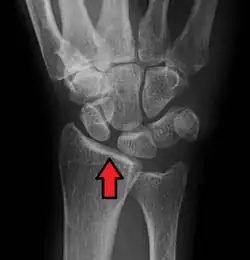

| Arrow pointing to the gap between scaphoid and lunate bones. Its name derives from Terry-Thomas, who had a similar looking gap between his two front teeth | |

In radiology, the Terry-Thomas sign is a scapholunate ligament dissociation on an anteroposterior view of the wrist.[1][2] Most commonly a result of a fall on the outstretched hand (FOOSH), the scapholunate ligament ruptures resulting in separation of the lunate and scaphoid bones. This burst causes the scaphoid bone to dorsally rotate.[3] A gap of more than 3mm is pathognomonic for scapholunate dissociation.[4]

The resulting separation between the scaphoid and lunate bones leaves a space on the x-ray that is similar to the gap comedian Terry-Thomas had between his front teeth. For newer radiology students who do not know who Terry-Thomas was, this finding might also be known as the David Letterman sign.[3]